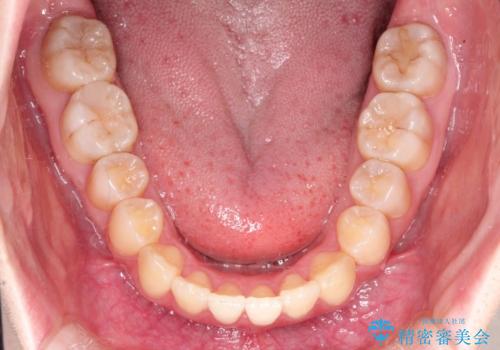

- 前歯のガタガタと、かみ合わせを改善したいとのことで来院されました。

人前でお話をするお仕事のため、装置をつけないでよいマウスピース矯正を希望されました。

下顎の歯が、上顎の歯に対して前方に位置していたので、下顎の歯を後方に移動させるのと、歯と歯の間を削りスペースを作り、歯を並べる計画としました。